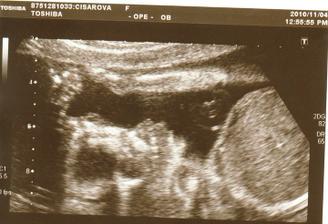

4.11. Velký UTZ v Motole. Čekáme holčičku!!! Všechno je v pořádku. Máme 465g a malá byla opravdu čiloušek.